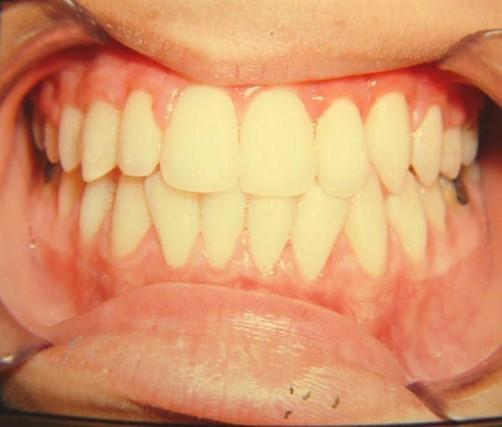

1η περίπτωση

Αρχική οδοντοσκελετική κατάσταση παιδιού με προγναθισμό άνω γνάθου και έντονη οριζόντια πρόταξη άνω τομέων Η σημασία της στοματικής υγιεινής και ορθοδοντικής

026

πρόληψης

027 Αμέσως μετά το τέλος της ορθοδοντικής θεραπείας. Οι αλλαγές στην οδοντική του σύγκλειση αλλά και στο πρόσωπο είναι εμφανείς 15 χρόνια μετά την αρχική περάτωση της θεραπείας, το αποτέλεσμα παραμένει σταθερό και ο ασθενής απέκτησε ένα υγιές και αρμονικό χαμόγελο και πρόσωπο. Η σημασία της στοματικής υγιεινής και ορθοδοντικής πρόληψης